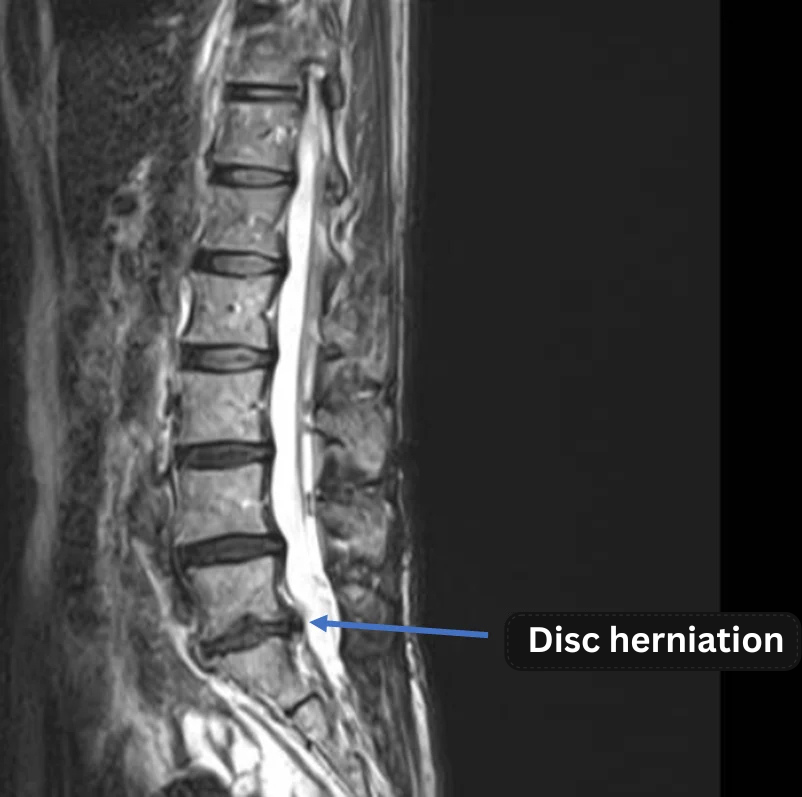

Imaging and findings

- L3/4, L4/5, L5/S: Disc degeneration

- L5/S: Lumbar disc herniation

The above findings were also observed on the imaging.

・Considering the clinical symptoms, the herniation at L5/S is highly likely to be the primary cause.